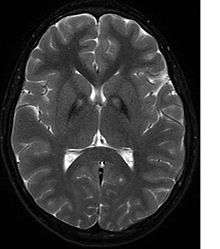

A neurological examination would show evidence of muscle rigidity; weakness; and abnormal postures, movements, and tremors. If other family members are also affected, this may help determine the diagnosis. Genetic tests can confirm an abnormal gene causing the disease. However, this test is not yet widely available. Other movement disorders and diseases must be ruled out. Individuals exhibiting any of the above listed symptoms are often tested using MRI (Magnetic Resonance Imaging) for a number of neuro-related disorders. As PKAN is a disease prominently evident in the brain, MRIs are very useful in making a sound diagnosis. An MRI usually shows iron deposits in the basal ganglia. Development of diagnostic criteria continues in the hope of further separating PKAN from other forms of neurodegenerative diseases featuring NBIA.

Diagnosis of PKAN hit a milestone with the availability of MRIs, as well as the in-depth descriptions of those MRIs provided by Littrup and Gebarski (1985),[10] Tanfani et al. (1987),[11] Sethi et al. (1988),[12] Angelini et al. (1992),[13] Casteels et al. (1994),[14] and Malandrini et al. (1995).[15] The gene was localized to chromosome 20p by Taylor et al. (1996) [16] who suggested that this disorder should be referred to as neurodegeneration with brain iron accumulation (NBIA1) to avoid the objectionable eponym of Hallervorden-Spatz. The disease was named 'pantothenate kinase-associated neurodegeneration' or PKAN by Zhou et al. (2001)[4] who suggested the name to avoid misinterpretation and to better reflect the true nature of the disorder. Most recently Pellecchia et al. (2005) published a report of 16 patients afflicted with PKAN, confirmed by genetic analysis.[17]